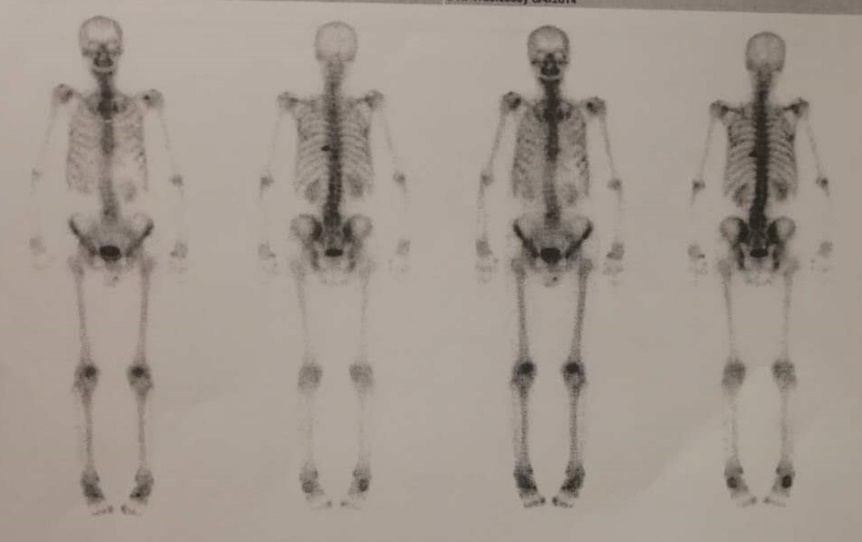

前列腺癌是典型的异质性肿瘤,由于发病隐匿,加之临床筛查工作尚未普及,所以高危进展性前列腺癌及转移性前列腺癌患者所占比例较高。其中,转移性激素敏感性前列腺癌(mHSPC)是转移性前列腺癌中预后较好的类型,但这一阶段的患者进展后将转变为转移性去势抵抗性前列腺癌(mCRPC),患者预后较差。目前,国内外多个权威指南均推荐泽珂®(醋酸阿比特龙片)用于mHSPC及mCRPC的一线治疗。本次为大家带来2例来自真实世界的病例分享,供读者交流和探讨。 病例一 病史 患者男性,78岁,主诉:前列腺特异性抗原(PSA)升高3年余。 现病史:患者3年余前体检发现PSA升高,约4.7ng/ml,后缓慢增高,未重视。2017年6月再次体检提示PSA 28.6ng/ml,外院行前列腺穿刺12针显示为前列腺腺泡腺癌,Gleason score 4+4。SPECT/CT提示全身骨转移(腰2,腰5可疑)。患者长期排尿不畅,夜尿增多(2-3次)。 直肠指诊:前列腺增大,双叶表面触及多处隆起结节质地硬,与直肠关系密切。 辅助检查 血常规:血红蛋白(Hb)126g/L,白细胞计数(WBC)4.7 x 10^9/L,血小板计数(PLT)132x10^9/L。 CT:髂血管旁淋巴结改变。 骨扫描:腰2转移腰5可疑。 图 髂血管旁淋巴结改变 图 全身骨显像 诊断结果 高危mHSPC(T3N1M1b,Gleason评分4+4=8分)。 治疗经过 2017年5月患者于外院应用5月内分泌治疗后,就诊于我院。 2017年11月患者内分泌治疗6月PSA下降至5.7ng/ml,加用原研阿比特龙1000mg联合泼尼松5mg Qd,PSA改善明显,至2020年4月,PSA下降至1.714ng/ml。 2020年7月PSA升至2.765ng/ml,遂将泼尼松换为地塞米松。 2021年4月,PSA为1.667ng/ml,月底更换国产阿比特龙。 2021年7月,PSA升至2.65ng/ml。 2021年8月,PSA为2.635ng/ml,换回原研阿比特龙。 病例分析: 本例患者为高危mHSPC患者,经内分泌治疗后,加用原研阿比特龙,PSA改善明显。国内外权威指南均推荐:醋酸阿比特龙是mHSPC患者的一线治疗方案2-4。LATITUDE研究对比了原研阿比特龙联合泼尼松(AAP)+雄激素剥夺疗法(ADT) vs 单用ADT治疗高危mHSPC患者的结果,数据显示,ADT+AAP显著延长高危mHSPC患者中位rPFS至33个月,对不同亚组的分析显示,ADT+AAP对于不同亚组高危mHSPC患者,均有一致的无进展生存期(PFS)获益,亚洲患者肿瘤转移进展风险降低近七成。原研阿比特龙组至PSA进展时间为33.2个月,对照组7.4个月,降低PSA进展风险70%。总生存期(OS)数据显示,安慰剂组中位OS为36.5个月。原研阿比特龙组为53.3个月,P值具有显著的统计学差异5。 图 LATITUDE研究结果 该患者使用原研阿比特龙32个月后,PSA显著改善,换用国产阿比特龙,PSA水平升高,这提示我们仿制药和原研药之间存在差异。原研阿比特龙是国际国内指南一线推荐治疗晚期前列腺癌的新型内分泌药物,相比仿制品,具有卓越的疗效及安全性证据。真实世界中,相比原研阿比特龙,仿制阿比特龙发生更多严重不良事件6-7。 病例提供者:马宏 教授 马宏 教授 北京医院泌尿外科 副主任医师 北京肿瘤防治研究会泌尿肿瘤委员会 副主委 北京抗癌协会泌尿肿瘤青年委员 北京中西医结合男科分会青年委员 中国研究型医院学会泌尿及男科冲击波学组委员 《中国性杂志》编委 北京大学医学部优秀教师 台大医院,柏林夏洛蒂医院访问学者 点评(万奔教授) 国产仿制药对于临床医生,多了可供选择的空间;对于患者,降低了部分支付压力。通常,仿制药的生物利用度在原研药生物利用度的80%~125%之内都认为两者具有生物等效性,但生物等效性在判定原则上会导致仿制药与原研药的生物利用度存在差异,而且会导致仿制药之间的生物利用度差异更大。在该病例中,患者换用国产阿比特龙后,PSA水平升高,提示生物等效性≠临床等效性8。对于部分高龄前列腺癌患者,基础合并疾病较多,生活质量普遍较差,如果非医疗原因换药,导致疾病波动及发生并发症的风险显著提高。因此,临床上应重点关注以上类型患者,谨慎权衡仿制药或原研药的选择9-12。期待未来中国制药产业技术的不断革新,国产仿制药品从品种到品质可以比肩原研药,保障更多患者获益。另外,此病例提示,阿比特龙联合治疗时,糖皮质激素的替换可带来患者的持续PSA减低。 点评专家:万奔 教授 万奔 教授 北京医院泌尿外科 主任医师 中国医师协会泌尿外科医师分会肿瘤专业委员会 委员 中国研究型医院学会泌尿外科学专业委员会 委员 北京抗癌协会泌尿男生殖系肿瘤专业委员会 副主任委员 北京医师协会泌尿外科专家委员会 委员 海峡两岸医药卫生交流协会泌尿外科学专业委员会 委员 中日医学科技交流协会 理事 病例二 病史 患者男性,69岁。主诉:体检发现PSA升高1周。 既往史:冠心病8年,3年前于外院行心脏冠脉支架置入术,长期口服阿司匹林和波利维抗血小板治疗。 辅助检查 实验室检查:总前列腺特异性抗原(T-PSA)149.5ng/ml。 骨扫描:右侧第3-5前肋、左侧第3/6前肋、第7后肋、第9后肋近肋椎关节处、第10胸椎、第2/5腰椎放射性摄取增高影(10处)。 前列腺MR增强:前列腺癌可能大,肿瘤突破包膜,累及精囊腺。双侧髂血管旁多发肿大淋巴结,转移可能。腰2、5椎体骨质破坏,转移可能大。 图 全身骨显像 穿刺病理:前列腺癌,12/13(+),Gleason 评分 4+5=9分,部分可见肿瘤浸润神经。 诊断结果 第一次诊断(2014年6月):高危mHSPC(T3bN1M1)。 第二次诊断(2015年2月):mCRPC。 治疗经过 2014年6月接受比卡鲁胺50mg Qd x 2w+戈舍瑞林10.8mg治疗。 2014年7月入组LATITUDE研究,PSA最低降至4.02 ng/ml。 2015年2月复查PSA升高至14.73 ng/ml,试验出组,揭盲,证实为安慰剂组;随后患者接受戈舍瑞林10.8mg+比卡鲁胺50mgQd,6个月后,PSA最低达到4.21 ng/ml。 2015年12月PSA升至9.12 ng/ml,停用比卡鲁胺,PSA水平于2016年2月回落至6.5ng/ml,8周后PSA再度上升至11.97ng/ml。 2016年6月患者接受阿比特龙1000mg Qd+泼尼松5mg Bid,PSA逐渐降低,最低至0.75ng/ml。 2017年11月将泼尼松5mg Bid换为地塞米松0.75mg Qd,PSA为2.36ng/ml。 2019年12月PSA水平缓慢上升到18.49 ng/ml,开始多西他赛+地塞米松方案化疗患者完成DP方案9周期化疗,PSA降至1.72ng/ml。 2020年7月患者因下腹隐痛行盆腔磁共振及PSMA-PET/CT检查示新发精囊转移灶,行放疗后,发现精囊癌灶变小,盆腔疼痛症状消失。 2020年11月PSA升高至3.4ng/ml,伴随新发后肋部疼痛,需口服镇痛药物缓解。复查PSMA和SSTR-PET/CT发现新发后肋部转移灶及多发肝脏病灶 ;行CT引导下肝脏病灶穿刺活检;病理:肝组织内见癌细胞浸润。 2020年11月23日多西他赛120mg+卡铂450mg化疗,化疗1周后出现中性粒细胞减低、血小板减低 CTCAE IV级,对症支持治疗1月后好转。 2021年1月开始应用恩杂卢胺治疗。 …… 图 前列腺癌患者不同治疗方案期间血清PSA水平变化情况 病例分析: 本例患者就诊时即发现全身多发骨转移,且Gleason评分4+5=9分,符合高危及高肿瘤负荷mHSPC诊断,2014年7月患者入组LATITUDE研究。LATITUDE研究为一项在新确诊为高危转移性未经激素治疗的前列腺癌患者中进行的多中心、3期、随机、双盲、安慰剂对照试验。最终分析显示,一线接受ADT+AAP的患者中位OS达4.5年,比一线接受ADT的患者延长16.8个月。因此,该患者无论接受单纯ADT,还是联合雄激素阻断治疗(CAB)都是不足够的,应首选推荐ADT联合阿比特龙的治疗方案。 图 LATITUDE研究结果 患者在mCRPC阶段应用阿比特龙联合泼尼松,经过数年的治疗,PSA控制良好,中间泼尼松换用地塞米松,继续维持阿比特龙使用,直至出现症状及影像进展。患者历经新型内分泌治疗等多种疗法,实现了长达7年的长期生存1。 病例提供者:米悦 教授 米悦 教授 北京大学第一医院 泌尿外科 主治医师 博士 北京大学泌尿外科研究所 擅长泌尿系肿瘤的微创治疗,前列腺增生、泌尿系结石的腔内治疗及晚期肿瘤的综合治疗。一直从事泌尿外科临床医疗、教学和科研工作。 2018年参加第32届“中国泌尿外科将才工程培训班”赴美国USC访问交流。累计发表国内核心期刊论文及SCI 论文6篇,参与撰写泌尿外科专著3部,翻译4部泌尿外科专著。 点评(张骞教授) 本例患者第一次被确诊为mHSPC,ADT治疗7个月后疾病快速进展为mCRPC。大部分高危/高瘤负荷的mHSPC患者在治疗初期ADT产生应答,但在ADT治疗9~15个月后发展为mCRPC。因此,对于高危mHSPC患者,临床应更早使用新型内分泌治疗。无论以PSA下降超过30%或50%作为界值,达到早期PSA应答(EPR)的患者预后均显著优于未达到EPR的患者。当患者进入mCRPC阶段后,应用ADT+AAP方案治疗1个月,患者PSA水平下降幅度达到73.4%,实现了EPR并且PSA较基线下降>50%。此后该方案在近3年内持续保持肿瘤相对控制和疾病稳定状态。该患者历经新型内分泌治疗、化疗、放疗、联合化疗和新型内分泌序贯治疗,取得了较好治疗效果,实现了长期生存。 点评专家:张骞 教授 张骞 教授 北京大学泌尿外科研究所 副所长 北京大学第一医院泌尿外科 副主任 北京大学滨海医院 院长 北京大学医学部医院管理处 处长 郭应禄泌尿外科发展基金会 副理事长 中国医师协会泌尿外科分会青年委员会 副主任委员 中华医学会泌尿外科学分会微创学组 委员 国家卫计委泌尿外科内镜诊疗技术专家组 委员 中国医促会腔镜内镜分会 常委 编者手札 在转移性前列腺癌患者的治疗过程中,通过监测PSA水平和影像学检查变化,能够及时了解患者对雄激素的敏感程度和疾病的进展情况,为治疗方案的调整和预后判断提供依据。原研阿比特龙是国际国内指南一线推荐治疗晚期前列腺癌的新型内分泌药物,首选原研阿比特龙能够为患者带来明显的PSA下降和持续的疾病控制。 备注:文中醋酸阿比特龙片简称阿比特龙 参考文献: 1.米悦,等.中华泌尿外科杂志.2021;42:19-23. 2.Advanced Prostate Cancer: AUA/ASTRO/SUO Guideline.2020. 3.European Association of Urology. Guidelines on Prostate Cancer. 2021. 4.NCCN Clinical Practice Guidelines in Oncology(NCCN Guidelines®) .2021.v2.. 5.CSCO,2021 前列腺癌诊疗指南 6.https://www.fda.gov/drugs/surveillance/fda-adverse-event-reporting-system-faers 7.Ryan CJ, et al. Lancet Oncol. 2015; 16(2):152-160. 8.黄浪,等.北方药学.2011;08(8):83-84. 9.resented by Prof. Gao Xin at 2018 CACA GU annual conference, Shanghai, Dec. 8, 2018. 10.马宝杰,等.中华泌尿外科杂志.2014;000(007):554-556. 11.Cheng Y, et al. Pharmacoepidemiol Drug Saf. 2019;28(11):1501–1509. 12.Holm M, et al. BMC Palliat Care. 2018 Dec 3;17(1):126.